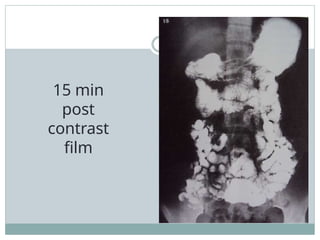

FILMING:

• Prone PA films of the abdomen are taken.

• The first radiograph is taken 10 min following the drink,

with the second image at 30 min stage. Then the

radiographs are taken at 30 min intervals until the

barium has reached terminal ileum.

• Pressure on the abdomen helps to compress abdominal

contents so that the loops of small bowel are separated.

Thus for better radiographic quality, prone position is

used.

• Spot films of the terminal ileum are taken supine.